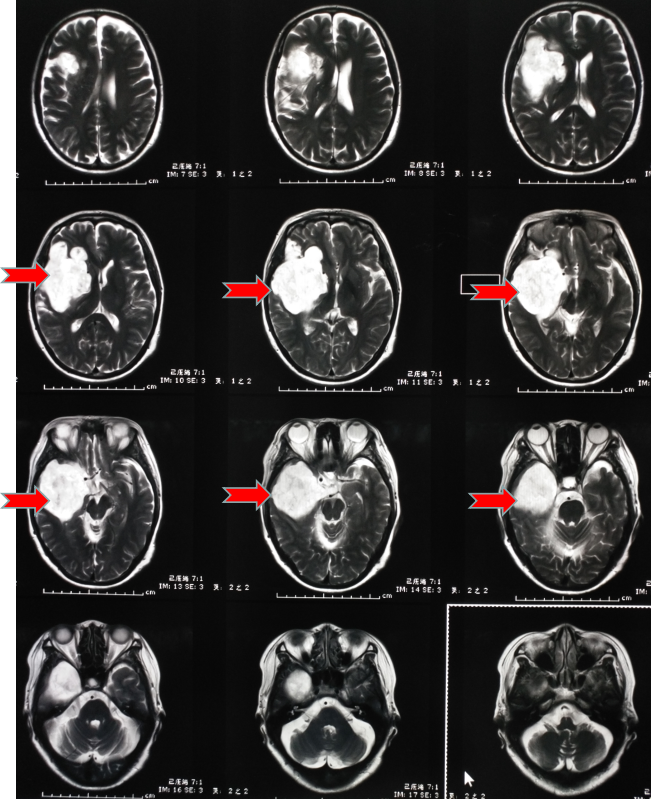

第二天趕緊到醫(yī)院看了一下,醫(yī)生說這是癲癇,隨后給她開了“丙戊酸鈉”長期口服,用藥后仍然每年有1-2次發(fā)作,大多是在晚上,有時(shí)即使沒有發(fā)生四肢抽搐,但有一種異樣的感覺。雖然這兩年很少發(fā)作了,但異樣感覺一直存在。今年她順利退休了,但教師的職業(yè)病——頸椎病卻讓他頸肩部以及上肢經(jīng)常麻木酸困,所以查了一下磁共振,確實(shí)存在頸椎病,但不需要手術(shù),只需保守治療即可。但意外的是發(fā)現(xiàn)了腦子里面長了個(gè)瘤子,大小約7厘米。

頭部磁共振提示腫瘤大小約7cm

一看片子,確認(rèn)是良性腫瘤,準(zhǔn)確點(diǎn)說應(yīng)該是一種叫做表皮樣囊腫的腫瘤,生長時(shí)間比較長,所以在早期很難發(fā)覺,經(jīng)常是在偶爾查頭部CT或者磁共振時(shí)發(fā)現(xiàn)。我給她說,這就是一直困擾她幾十年的病根所在,只要將它切除,她的癲癇和異樣感會(huì)逐漸消退,否則,隨著腫瘤增大,不僅會(huì)癲癇反復(fù)發(fā)作,而且會(huì)影響其他神經(jīng)功能??紤]再三,最終她還是選擇手術(shù)治療。

顱內(nèi)膽脂瘤的發(fā)病率為全腦腫瘤的0.5-1.8%??蔀槎喟l(fā),大小由幾毫米至數(shù)厘米不等。顱內(nèi)膽脂瘤目前認(rèn)為系胚胎期(妊娠3-5周)神經(jīng)管閉合時(shí)混入了外胚層成分所導(dǎo)致。沒有遺傳易感性,沒有易感基因,它的發(fā)病跟孕期孕婦營養(yǎng)不足或受到有毒物質(zhì)輻射有關(guān),導(dǎo)致胎兒的神經(jīng)管不能正常形成;顱內(nèi)膽脂瘤好發(fā)于鞍區(qū)、顱中窩和后顱窩,發(fā)生在后顱窩,壓住了面神經(jīng)和位聽神經(jīng),就會(huì)出現(xiàn)聽力下降、面部癱瘓,壓迫三叉神經(jīng),會(huì)出現(xiàn)繼發(fā)性三叉神經(jīng)痛,如壓迫后組顱神經(jīng),會(huì)產(chǎn)生飲水嗆咳和咽部麻痹癥狀,腫瘤在顱中窩,壓迫動(dòng)眼神經(jīng)會(huì)產(chǎn)生眼球活動(dòng)障礙、眼瞼下垂,鞍區(qū)的顱內(nèi)膽脂瘤,如在視丘下部,會(huì)導(dǎo)致病人意識(shí)朦朧、模煳,產(chǎn)生在垂體,會(huì)造成女性月經(jīng)失調(diào),男女不孕不育,電解質(zhì)紊亂會(huì)造成多飲、多尿或視力減退;顱內(nèi)膽脂瘤惡變幾率非常小,但如果不及時(shí)干預(yù),腫瘤長大后會(huì)破裂,會(huì)造成腦組織炎癥,導(dǎo)致病人顱內(nèi)壓增高,甚至唿吸驟停;顱內(nèi)膽脂瘤發(fā)病率占顱內(nèi)腫瘤的1.5%-2%,男女發(fā)病比例為1.25:1,一般多在20-40歲產(chǎn)生癥狀,跟地域和飲食、生活習(xí)慣等都沒有關(guān)系。顱內(nèi)膽脂瘤的治療一般以手術(shù)治療為主,宜手術(shù)切除,然而因腫瘤與血管粘連緊密,國內(nèi)外很多專家認(rèn)為完全切除是不明智的,且應(yīng)避免,以免致殘或死亡,術(shù)后復(fù)發(fā)時(shí)間一般為數(shù)年,長者可達(dá)十幾年,術(shù)后復(fù)發(fā)率為5%。所以術(shù)后應(yīng)定期到醫(yī)院復(fù)查,如果復(fù)發(fā)可以再次手術(shù),預(yù)后還是比較理想的。